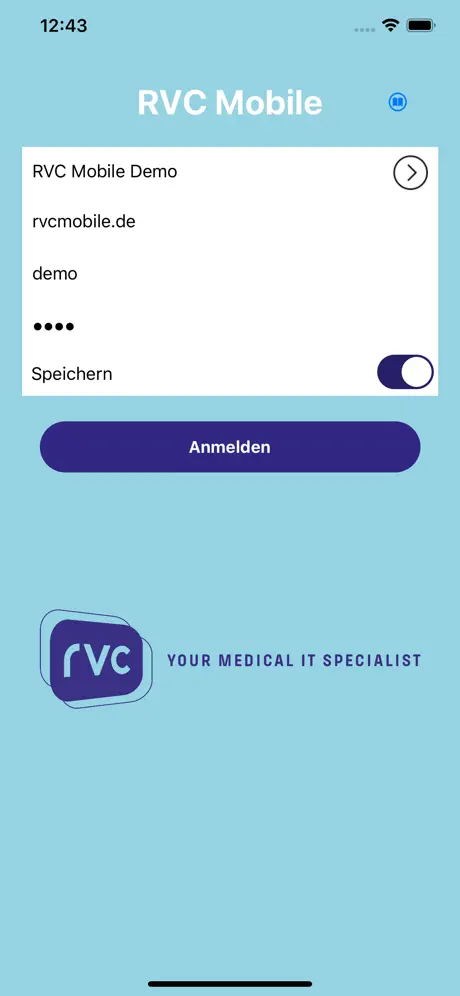

Die RVC Mobile App ist eine native iOS Applikation welche sicher

mit dem einheitlichen RVC Server kommuniziert. Mit dieser App werden iPAD, iPod touch und iPhone zu mobilen Clients die Inhalte aus RVC Clinical PACS / mDMAS intuitiv anzeigen. Dadurch ist ein ortsunabhängiger Zugriff auf das multimediale Archiv möglich. Als Mehrwert dieser Clients wurde auch eine Foto- und Videodokumentation mit integriert, sodass Fotos oder auch Videos direkt vom mobilen Endgerät in das Archiv gespeichert werden können.

Auf dem Endgerät selbst werden keine patientenbezogenen Daten dauerhaft abgespeichert.

- Logindialog zur Authentifizierung

- Logindialog zur Authentifizierung